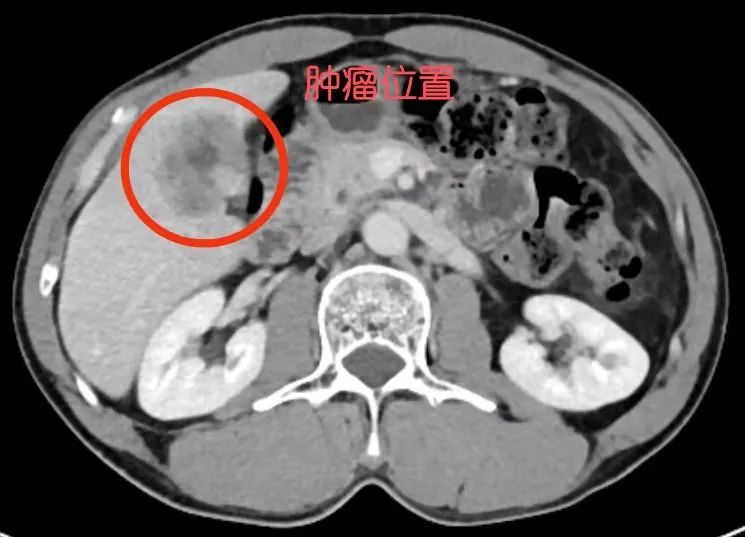

据悉,43岁的黄先生因在县级医院检查发现“肝占位十余天”,后因当地条件有限遂转至我院肝胆外科进一步治疗,经详细检查发现肝脏有一4cmX4cm×3cm大小的肿瘤,且肿瘤呈进行性增大,若不及时手术,会加大自发性或外伤性破裂出血的风险。

患者术前肝肿瘤CT情况